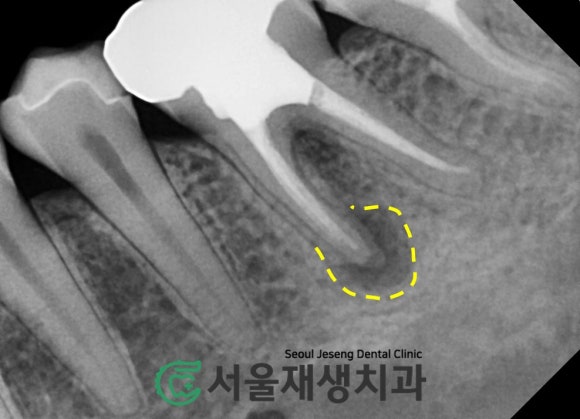

치아 뿌리 끝에서 시작된 염증이

주위의 뼈를 녹이고 있습니다.

아하,

뿌리끝 주위로

까맣게 보이는 빈공간은

다름 아닌

염증으로 인해

뼈가 흡수된 공간이로군요!